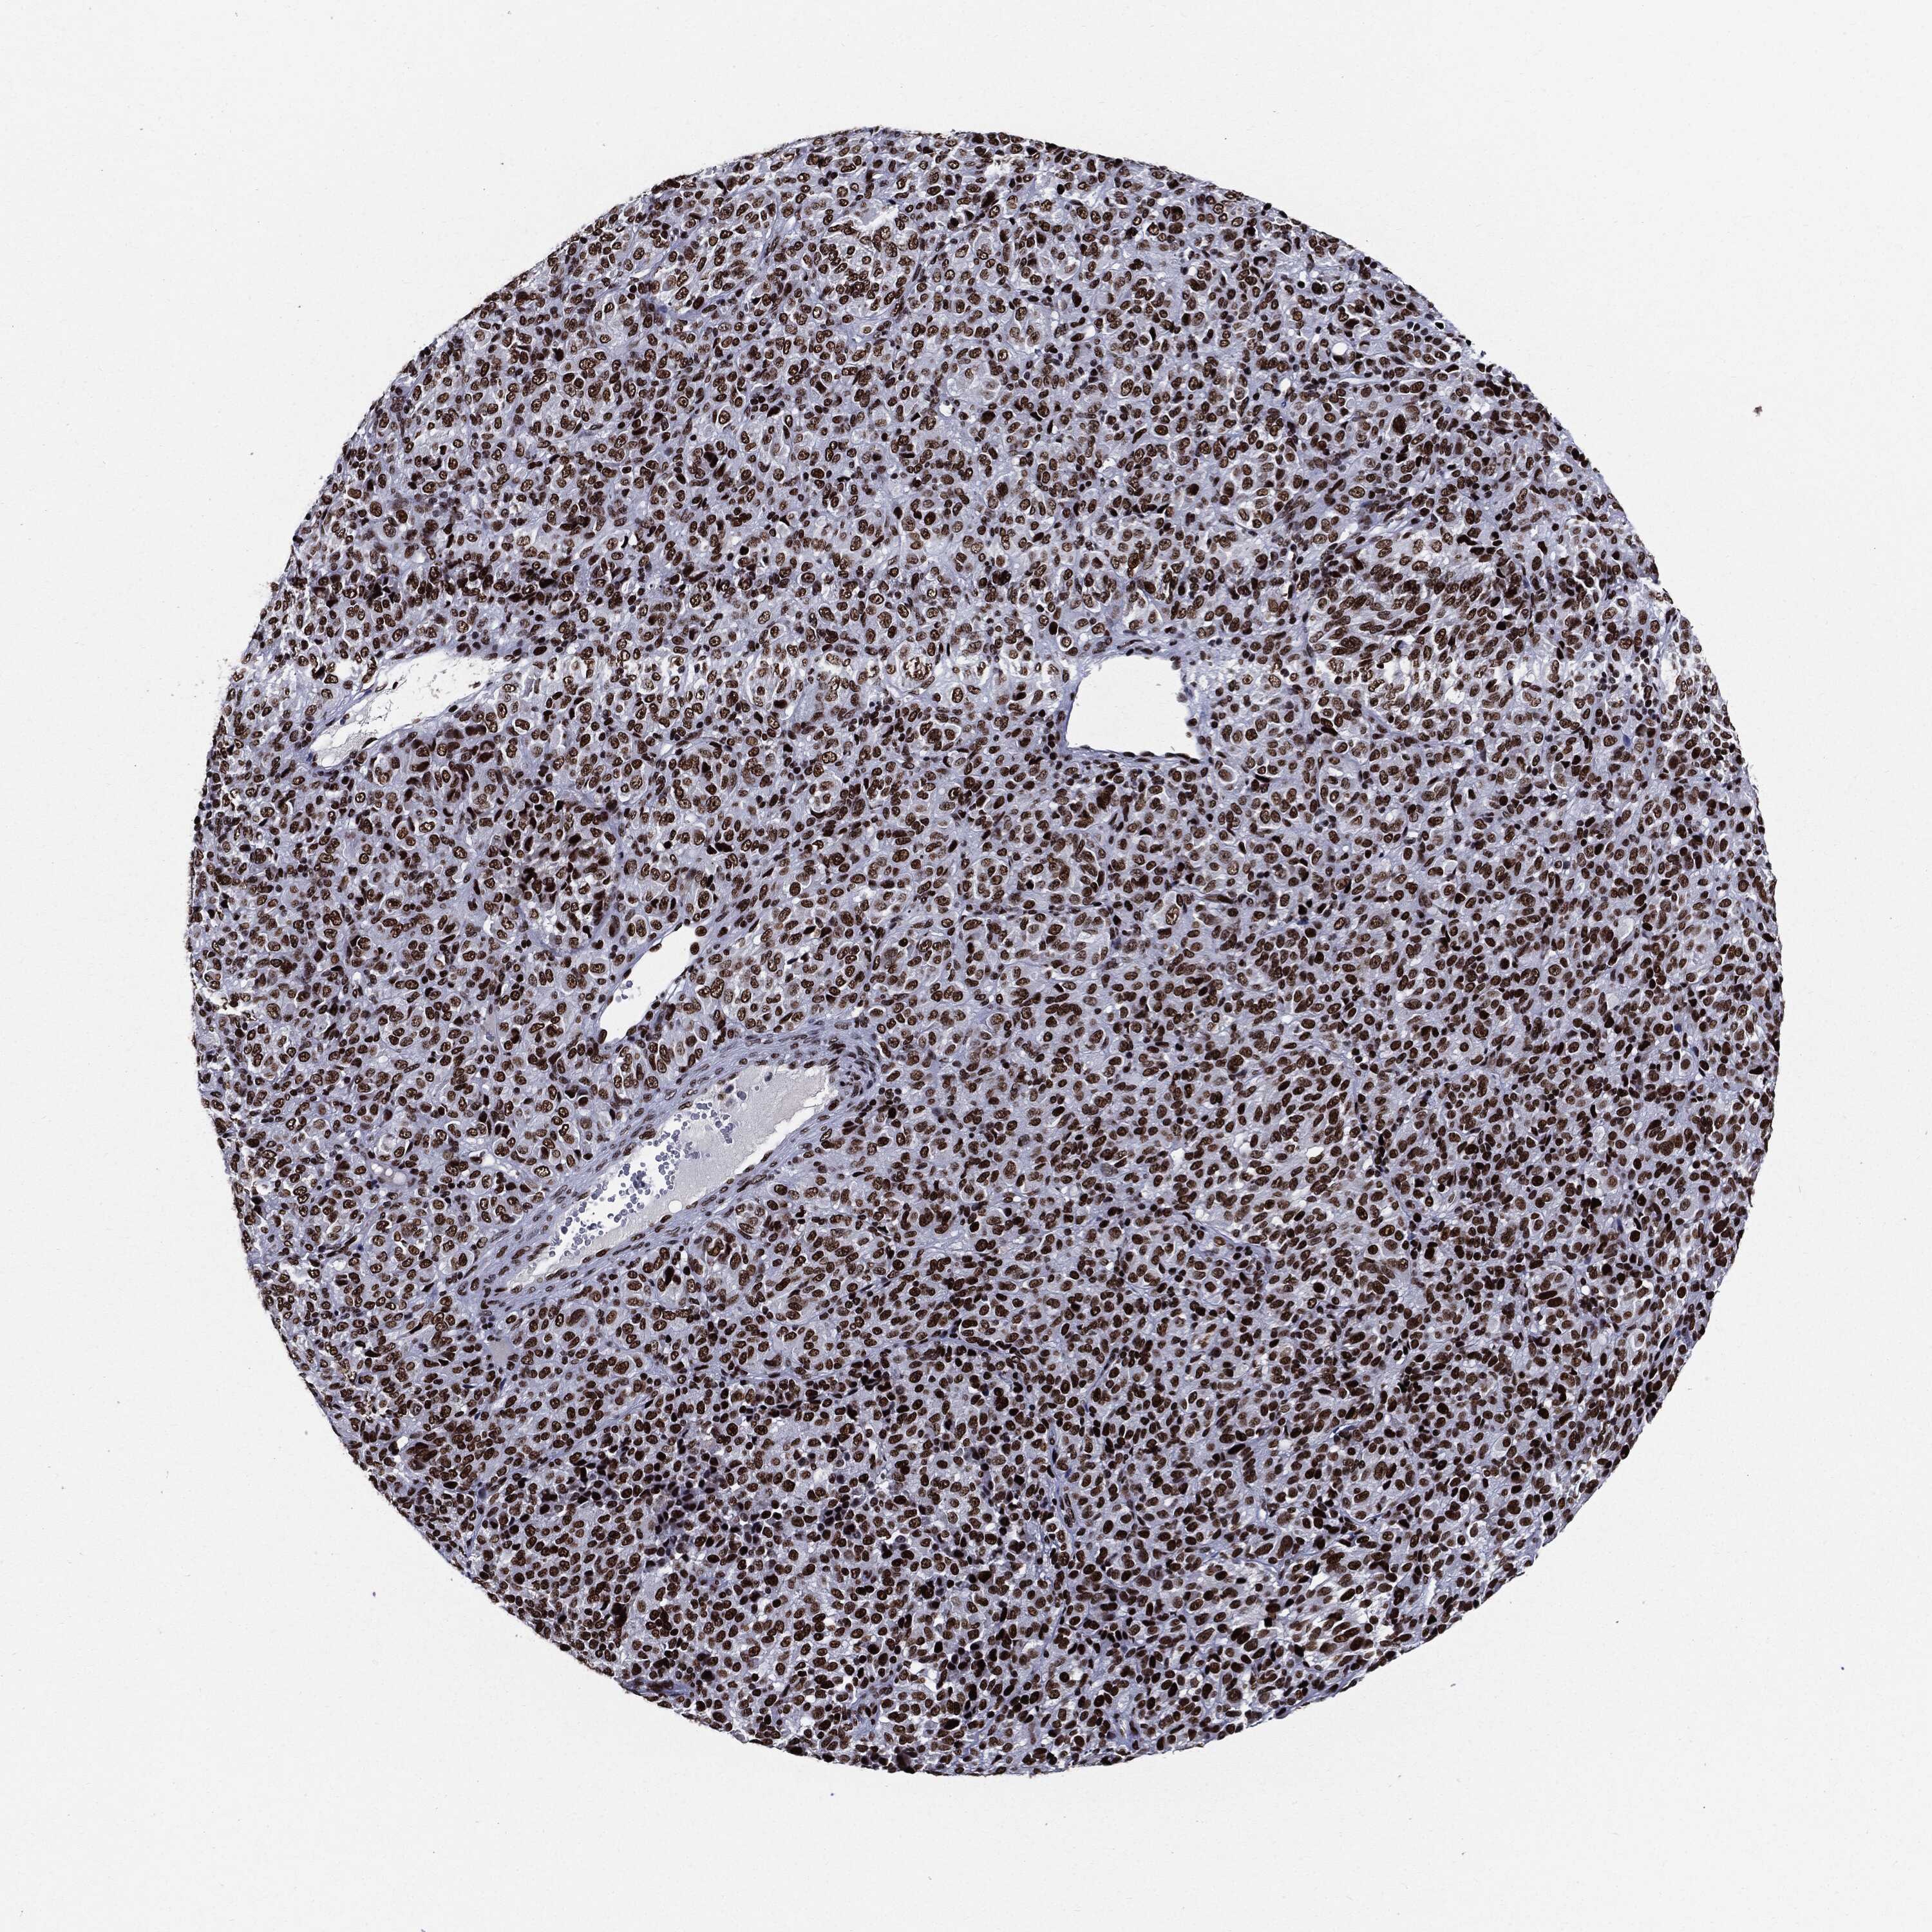

MELANOMA - Protein expressioni

A mouse-over function shows sample information and annotation data. Click on an image to view it in a full screen mode. Samples can be filtered based on level of antibody staining by selecting one or several of the following categories: high, medium, low and not detected. The assay and annotation is described here.

Note that samples used for immunohistochemistry by the Human Protein Atlas do not correspond to samples in the TCGA dataset.

Antibody stainingi

Antibody staining in the annotated cell types in the current human tissue is reported as not detected, low, medium, or high, based on conventional immunohistochemistry profiling in selected tissues. This score is based on the combination of the staining intensity and fraction of stained cells.

Each image is clickable and will lead to virtual microscopy that enables deeper exploration of all samples and also displays staining intensity scores, fraction scores and subcellular localization as well as patient and tissue information for each sample.

Antibody HPA024037

Antibody HPA065325

Antibody HPA074591

Antibody CAB025417

Staining

High

Medium

Low

Not detected

Intensity

Strong

Moderate

Weak

Negative

Quantity

>75%

75%-25%

<25%

None

Location

Nuclear

Cytoplasmic/membranous

Cytoplasmic/membranous,nuclear

Malignant melanoma, NOS

Malignant melanoma, Metastatic site